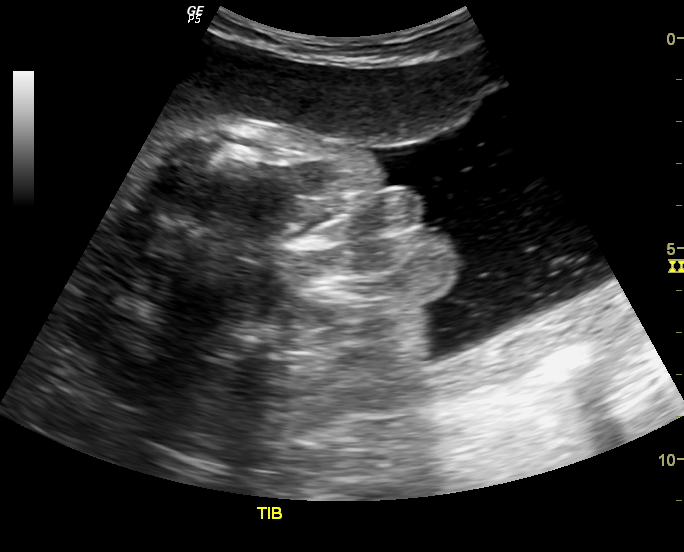

This is what we found when we did the colour Doppler study of the left lower limb.

This patient did not have any major pain or tenderness in the thigh.Clinically, he did not have features of deep vein thrombosis. Would you think of this possibility from these Doppler ultrasound images?

The answer: this is a case of Left femoral vein thrombosis. There is near total absence of flow signal in a major part of the left femoral vein. The lack of symptoms is explained by the patient having had anticoagulant treatment for a few days.